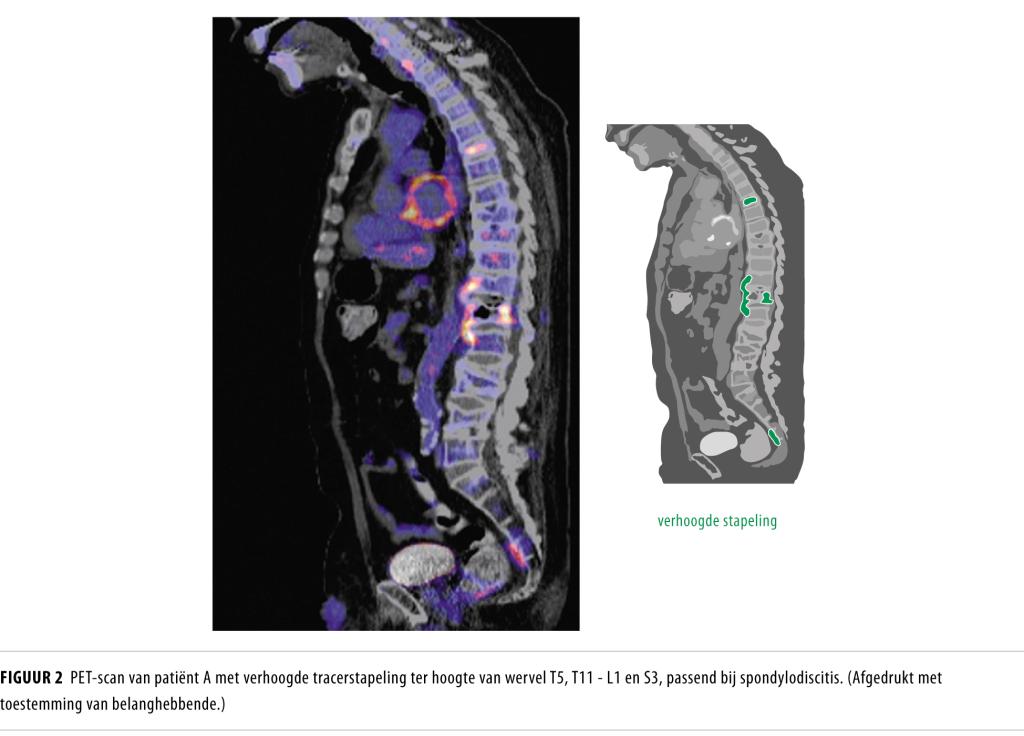

Een week na ontslag werd hij vanwege deze klachten opgenomen op de afdeling Geriatrie. Bij opname was er sprake van kloppijn over de onderste thoracale wervel, verminderde sensibiliteit in het rijbroekgebied, en levendige reflexen, verminderde kracht en voetzoolreflexen volgens Babinski aan beide benen. Het laboratoriumonderzoek toonde een CRP-concentratie van 110 mg/l en een leukocytenaantal van 13,6 x 109/l. Op de MRI-scan van de wervelkolom zag de radioloog een inzakking van de 5e thoracale wervel met tekenen van werveloedeem, mogelijk door een wervelmetastase, een mogelijke metastase van de 12e thoracale wervel en 2 bekende lumbale wervelinzakkingen (figuur 1).

De casus van patiënt kwam ook aan de orde tijdens de oncologiebespreking, waar het sterke vermoeden werd uitgesproken dat patiënt wervelmetastasering had met een bijkomende infectie anders dan spondylodiscitis. Het antibioticum werd vervolgens gestaakt, waarna de ontstekingswaarden weer stegen en de rugpijn toenam. Op zoek naar een eventuele primaire tumor werd een FDG-PET-CT-scan verricht. Hierop zagen wij een beeld dat paste bij spondylodiscitis op meerdere wervelniveaus (T5-T6, T11-L1 en S2-S3) (figuur 2). De bloedkweken, afgenomen vóór aanvang van de antibiotica, bleven negatief.